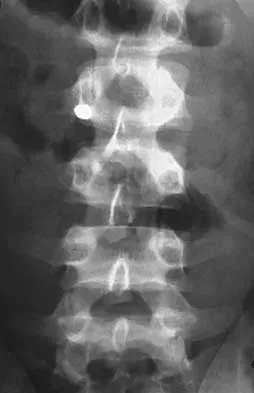

Figures 9a and 9b show the spinal radiographs of a 3-year-old child with short limb dwarfism. The lateral radiograph is obtained with maximal lumbar extension. Management should consist of

Explanation

The patient has kyphosis in association with achondroplasia. The AP radiograph shows decreased interpedicular distance at the lower lumbar vertebrae, a feature considered to be a distinctive sign of achondroplasia. Most patients with achondroplasia have kyphosis, and this usually resolves spontaneously. When the fixed component is greater than 30 degrees, however, brace treatment is recommended. Spinal fusion is seldom required.